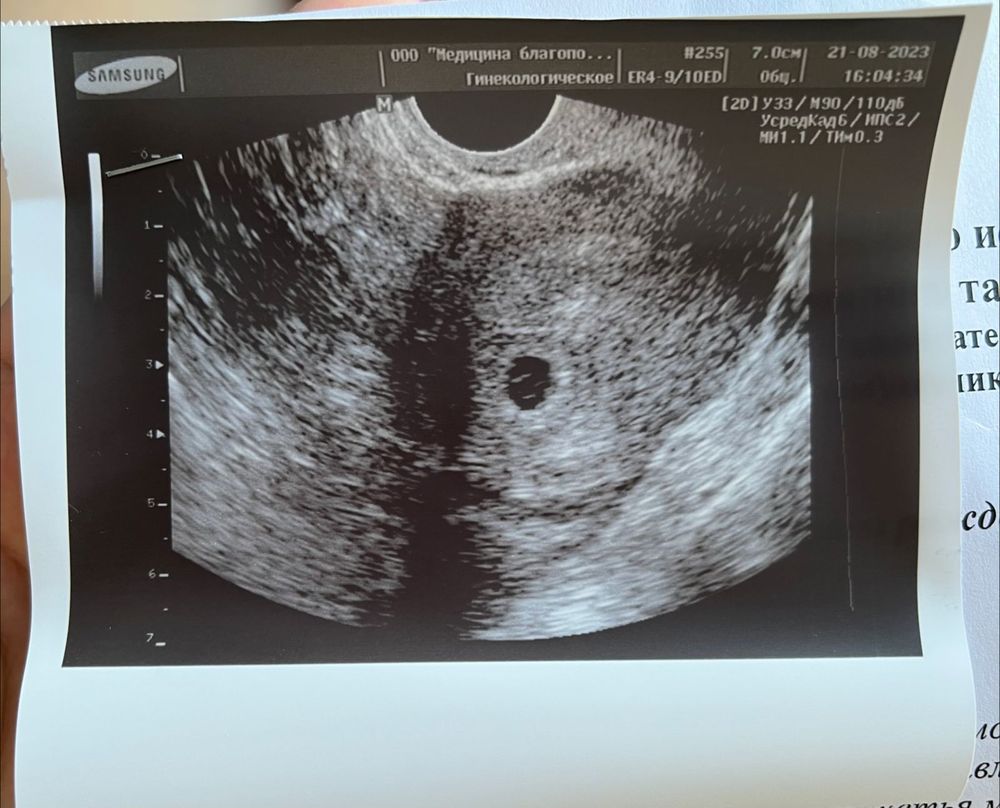

Овуляция была где то на 18-19 ДЦ. Сегодня пошла узи, все там хорошо, кроме одного-пока не видят эмбриона. Говорит, по идее уже сердцебиение должно быть. Возможно, было позднее прикрепление. Я что то волноваться начала. Никакие диагнозы не ставят, сказали подойти через 7-10 дней на контрольное узи. Потом вставать на учет по беременности. Девочки, подскажите, у кого так было? Малыша нашли? Это вторая беременность. Первая зб.

Ходила на узи на 5 недель и 1 день. Было ПЯ 8мм и желточный мешочек 2,1мм, но малыша не видно, сердцебиение не слышно. Рано нам еще на таком сроке) главное, что беременность маточная, а малыш появится через 7-10 дней)